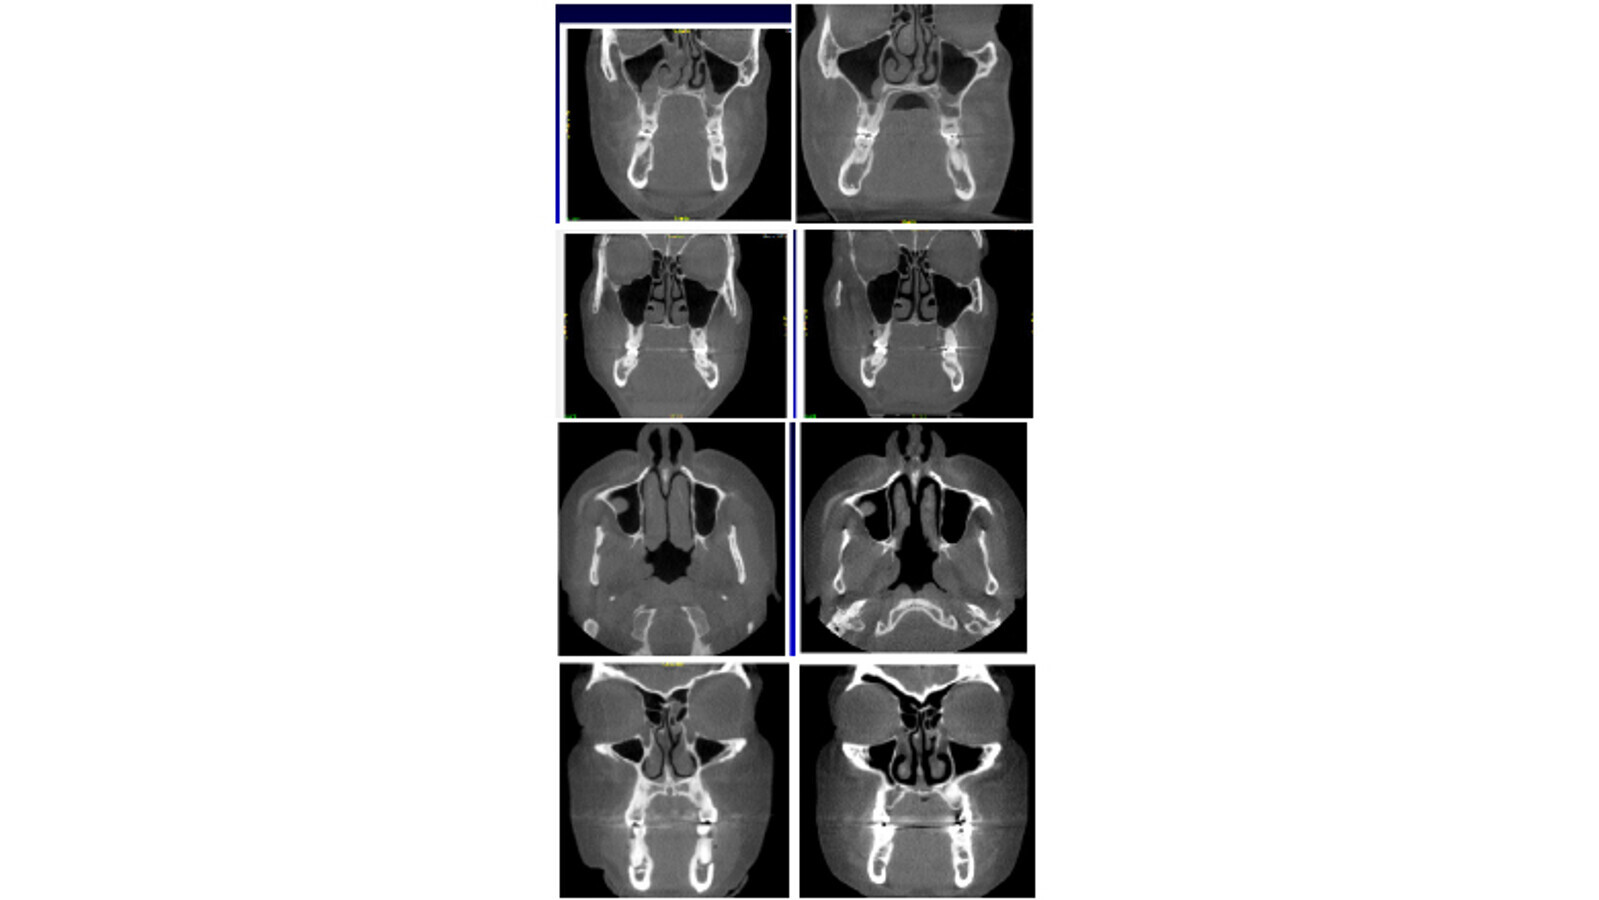

Vea los patrones de desarrollo facial, que se muestran en rojo en 5 pacientes seleccionados al azar, antes y después del tratamiento (Figura 3).

Figura 3. El color rojo muestra un ensanchamiento en el área nasal anterior del maxilar superior, como si tuviera implantado una tira nasal de respiración permanente.